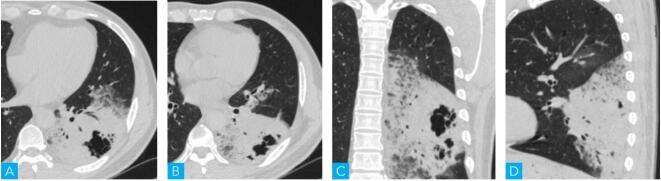

该患者入院后行胸部CT平扫检查,层厚为5mm,层间隔5mm,电压100kV,电流200~280mA,矩阵512×512(图1)。

图1 胸部CT平扫图像

A~D. 横轴位与冠、矢状位CT肺窗图像

该病例的CT表现具有相对特征性,左肺下叶实变,实变边缘呈磨玻璃密度,实变内见充气支气管征及蜂窝状空腔,病变呈肺叶分布,叶间裂局部膨隆。认真细致观察影像图像,并善于抓住特征性表现,做出B项的正确选择并不难。

2.诊断要点

本病例的肺叶实变具有相对特征性,即边缘较清晰的软组织密度与磨玻璃密度混合存在的肺叶实变,且实变具有部分膨胀性,实变区域内具有扩大的含气囊腔-“假空洞”征。具有膨胀性的肺叶实变,提示病灶具有增殖性,“假空洞”征可能是因支气管壁受到肿瘤细胞浸润,管腔僵硬狭窄,活瓣作用所致局部肺组织扩张,气体潴留所致,再结合患者主要症状为咳清水痰,提示肺泡腔内可能充满黏液。上述要点符合支气管肺癌的一种特殊类型即弥漫性浸润性肺腺癌的影像学及临床特点。

该病例最终病理诊断:“左肺下叶浸润性黏液腺癌,乳头型为主”。梳理临床上有价值的病史,患者咳清水样痰而不是脓痰提示肺内可能存在黏液,再加上肺癌标志物升高,更加提示肿瘤性病变可能性增加。CT上表现为左肺下叶实变,边缘部趋磨玻璃密度,病灶内见充气支气管征以及“假空洞”征。病变呈叶段性分布,但仔细观察可见左肺下叶体积增大,叶间裂稍膨隆,而不是收缩提示该实变具有增殖性。这些临床及CT表现均提示弥漫性浸润性黏液腺癌。实变内充气支气管征的形态以及“假空洞”征为弥漫性浸润性黏液腺癌CT平扫较为特征性的改变,对诊断有较大帮助。